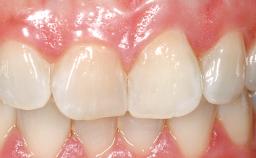

Late Flapless Placement of an Implant in a Maxillary Left Central Incisor Site

A 39-year-old male patient presented with a chief complaint of discomfort and gingival discoloration around his maxillary left central incisor. He was in good general health and was a non-smoker. His past dental history was significant because of the traumatic fracture of tooth 21 in a sporting accident at age 13. Initial dental treatment included endodontic therapy and a full-coverage restoration. The patient became symptomatic 5 years later, when structural failure of the tooth resulted in the dislodgment of the crown. Endodontic retreatment, apical surgery, and post-and-core restoration were performed.

Prosthesis Type FDP

SAC Level Advanced

Defining Characteristics One missing tooth to be replaced by an implant-borne crown